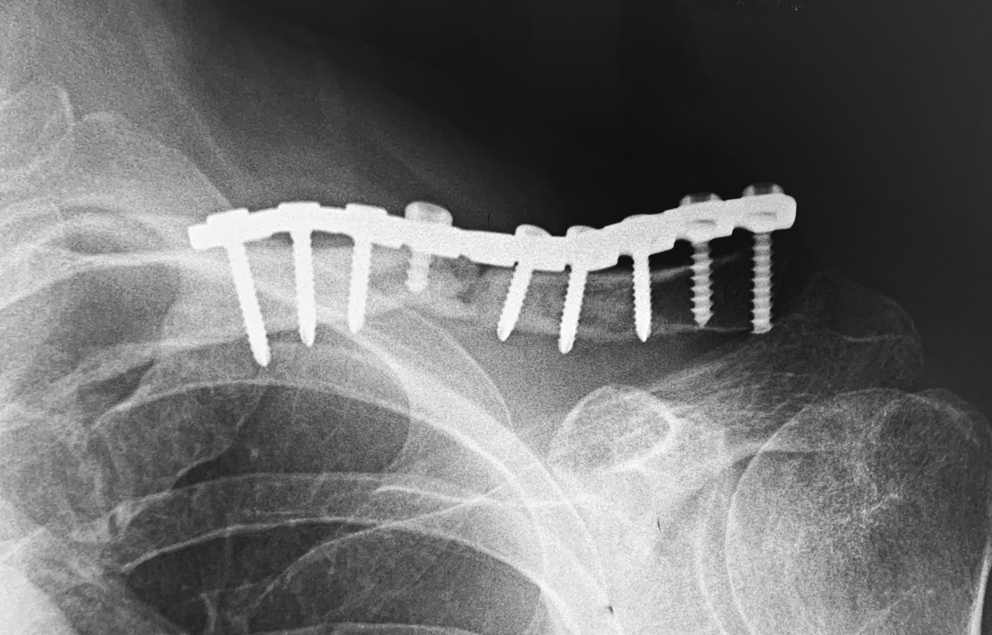

Пациент 70 лет в марте 2018 г. в результате падения получил перелом средней трети диафиза левой ключицы. В течение четырех месяцев он проходил консервативное лечение в амбулаторных условиях, закончившееся формированием несращения (рис. 1 а).

В одном из стационаров города был выполнен накостный остеосинтез левой ключицы пластиной АО 1/3 трубки с угловой стабильностью в сочетании со серкляжным швом (рис. 1 b).

Рис. 1. Рентгенограмма ключицы пациента: а — при поступлении;b — после накостного остеосинтеза